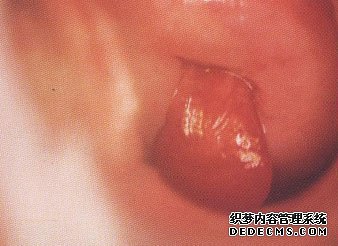

宫颈息肉图片

宫颈息肉图片1: